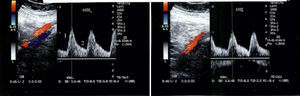

In 2007, her blood pressure remained uncontrolled and the patient complained of intense bilateral lower limb muscular fatigue, without calf pain. Arterial Doppler ultrasound was performed that revealed a symmetrically decreased ankle/brachial pressure index and persistent blood flow during diastole, suggesting abdominal aortic stenosis (Figure 2).